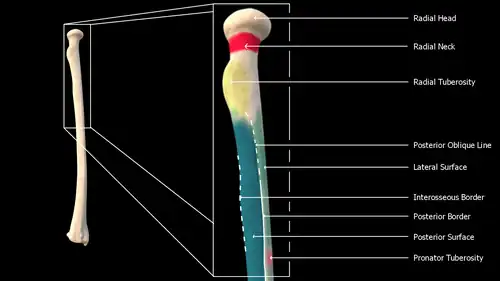

Body

The body of the radius (or shaft of radius) is prismoid in form, narrower above than below, and slightly curved, so as to be convex lateralward. It presents three borders and three surfaces.

- Borders

The volar border (margo volaris; anterior border; palmar;) extends from the lower part of the tuberosity above to the anterior part of the base of the styloid process below, and separates the volar from the lateral surface. Its upper third is prominent, and from its oblique direction has received the name of the oblique line of the radius; it gives origin to the flexor digitorum superficialis muscle (also flexor digitorum sublimis) and flexor pollicis longus muscle; the surface above the line gives insertion to part of the supinator muscle. The middle third of the volar border is indistinct and rounded. The lower fourth is prominent, and gives insertion to the pronator quadratus muscle, and attachment to the dorsal carpal ligament; it ends in a small tubercle, into which the tendon of the brachioradialis muscle is inserted.

The dorsal border (margo dorsalis; posterior border) begins above at the back of the neck, and ends below at the posterior part of the base of the styloid process; it separates the posterior from the lateral surface. is indistinct above and below, but well-marked in the middle third of the bone.

The interosseous border (internal border; crista interossea; interosseous crest;) begins above, at the back part of the tuberosity, and its upper part is rounded and indistinct; it becomes sharp and prominent as it descends, and at its lower part divides into two ridges which are continued to the anterior and posterior margins of the ulnar notch. To the posterior of the two ridges the lower part of the interosseous membrane is attached, while the triangular surface between the ridges gives insertion to part of the pronator quadratus muscle. This crest separates the volar from the dorsal surface, and gives attachment to the interosseous membrane. The connection between the two bones is actually a joint referred to as a syndesmosis joint.

- Surfaces

The volar surface (facies volaris; anterior surface) is concave in its upper three-fourths, and gives origin to the flexor pollicis longus muscle; it is broad and flat in its lower fourth, and affords insertion to the Pronator quadratus. A prominent ridge limits the insertion of the Pronator quadratus below, and between this and the inferior border is a triangular rough surface for the attachment of the volar radiocarpal ligament. At the junction of the upper and middle thirds of the volar surface is the nutrient foramen, which is directed obliquely upward.

The dorsal surface (facies dorsalis; posterior surface) is convex, and smooth in the upper third of its extent, and covered by the Supinator. Its middle third is broad, slightly concave, and gives origin to the Abductor pollicis longus above, and the extensor pollicis brevis muscle below. Its lower third is broad, convex, and covered by the tendons of the muscles which subsequently run in the grooves on the lower end of the bone.

The lateral surface (facies lateralis; external surface) is convex throughout its entire extent and is known as the convexity of the radius, curving outwards to be convex at the side. Its upper third gives insertion to the supinator muscle. About its center is a rough ridge, for the insertion of the pronator teres muscle.[3] Its lower part is narrow, and covered by the tendons of the abductor pollicis longus muscle and extensor pollicis brevis muscle.

Near the elbow

The upper extremity of the radius (or proximal extremity) presents a head, neck, and tuberosity.

- The radial head has a cylindrical form, and on its upper surface is a shallow cup or fovea for articulation with the capitulum (or capitellum) of the humerus. The circumference of the head is smooth; it is broad medially where it articulates with the radial notch of the ulna, narrow in the rest of its extent, which is embraced by the annular ligament. The deepest point in the fovea is not axi-symmetric with the long axis of the radius, creating a cam effect during pronation and supination.

- The head is supported on a round, smooth, and constricted portion called the neck, on the back of which is a slight ridge for the insertion of part of the supinator muscle.

- Beneath the neck, on the medial side, is an eminence, the radial tuberosity; its surface is divided into a posterior, rough portion, for the insertion of the tendon of the biceps brachii muscle, and an anterior, smooth portion, on which a bursa is interposed between the tendon and the bone.

Radius l. dx. – post. view

Radius l. dx. – post. view -